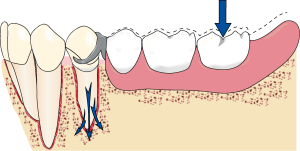

When a mesial occlusal rest and a reverse Akers clasp, approaching the distobuccal undercut from the mesio-occlusal surface are used in distal extension dentures, as the denture base moves toward the tissue, the clasp tip moves into a deeper undercut area, and no torque is generated on the abutment tooth.

When occlusal load is applied to the denture base, the tip of the retentive arm moves gingivally, entering a deeper undercut and thus moving away from the tooth surface. This prevents the generation of torque on the abutment tooth. The advantage of this design lies in the extension of the lever arm, which represents the distance between the rest and the denture base. This increase in length causes the rotational movement of the denture base to become more upright in the ridge area during function. Vertical forces are better tolerated compared to horizontal oblique forces.

Although the mesial occlusal rest and distobuccal undercut approach have some planning advantages, the rigid horizontal reciprocal arm involved in this design generates stress in the mesiolateral direction on the abutment tooth. It should be noted that the reciprocal arm is positioned on the survey line and moves gingivally when occlusal load is applied to the base. Therefore, unlike the retentive arm that moves away from the abutment tooth, the rigid reciprocal arm generates stress on the buccal side of the abutment tooth when it is forced downward on the survey line.